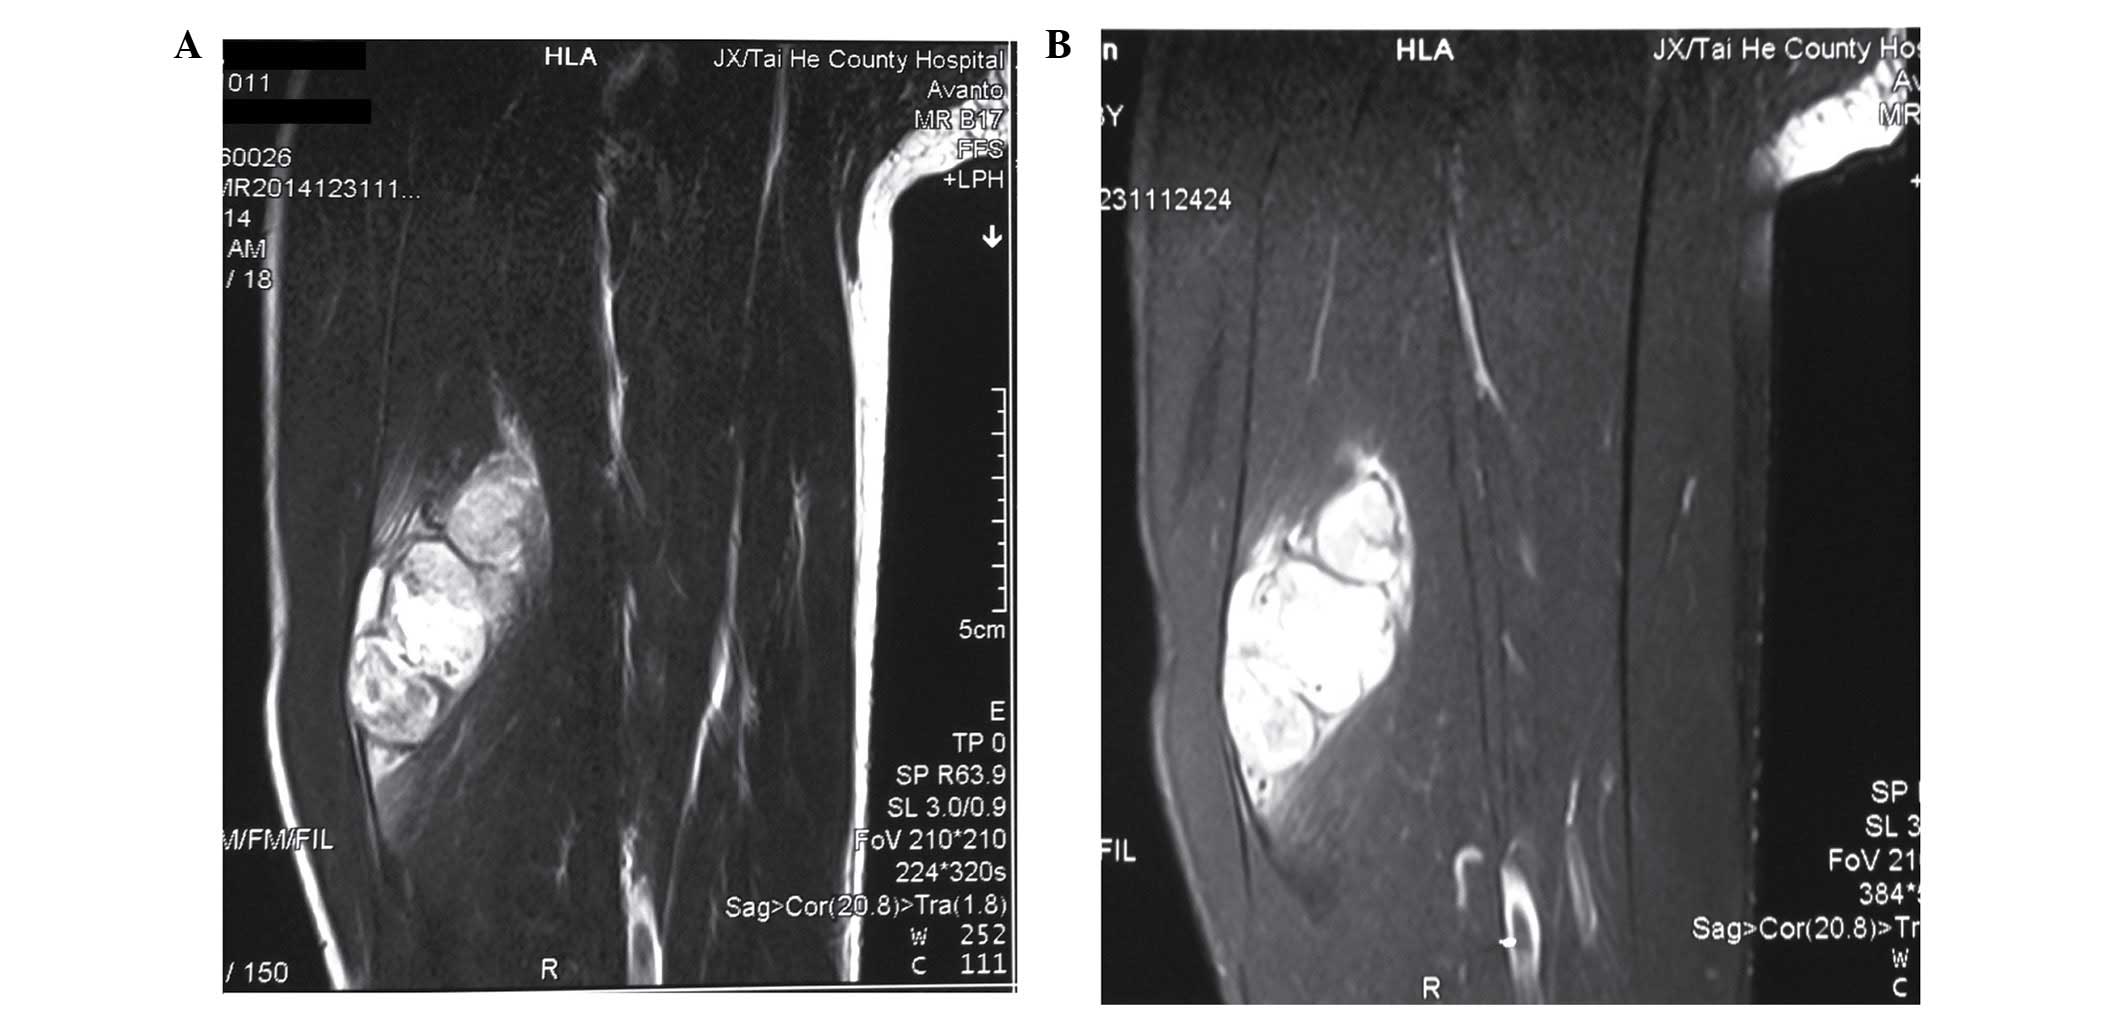

Rhabdomyosarcoma - Pathology - Orthobullets

www.orthobullets.com

www.orthobullets.com

rhabdomyosarcoma orthobullets mri pathology 51a donnell patrick topic

Successful Treatment Of Adult Pleomorphic Rhabdomyosarcoma In The

www.scirp.org

www.scirp.org

rhabdomyosarcoma femur mri pleomorphic posterior treatment thigh examination mass